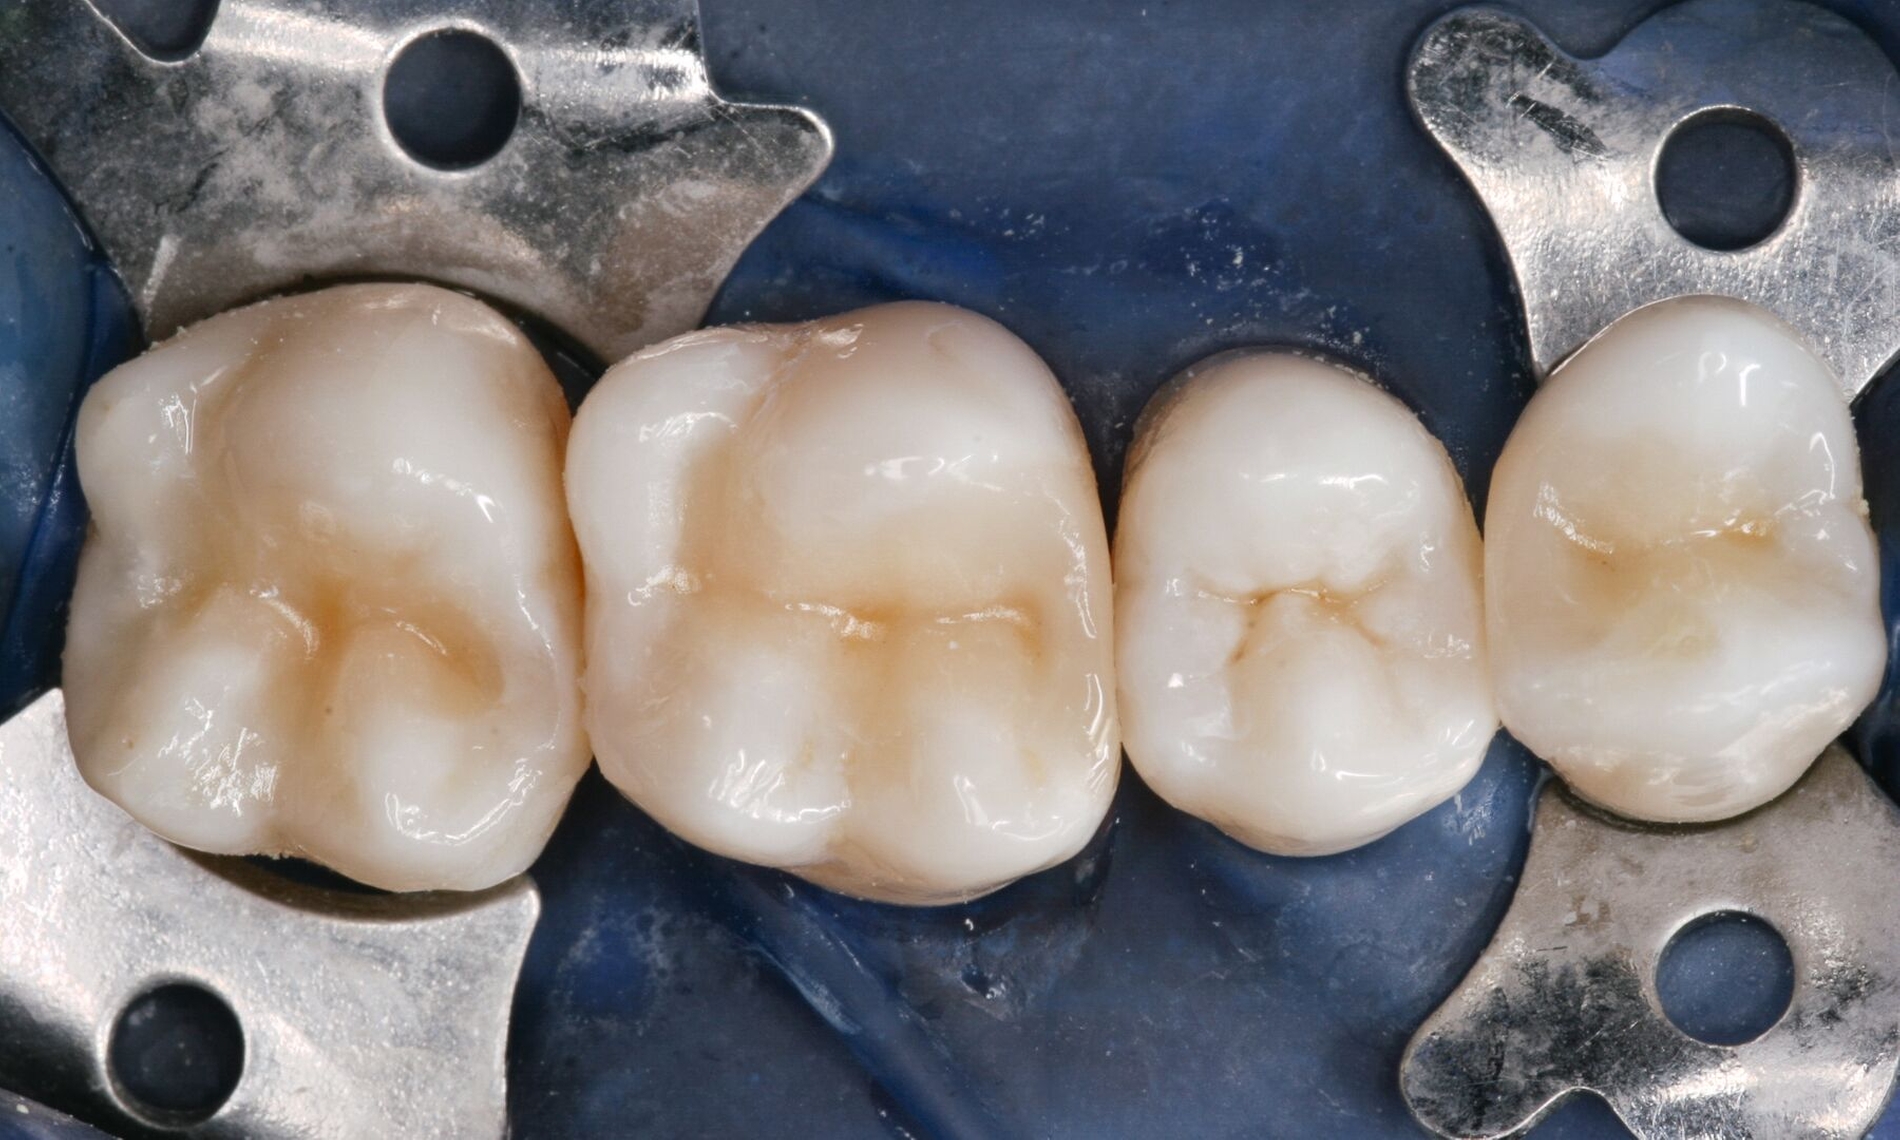

Für solche tiefen Areale existieren zwei unterschiedliche Lösungsansätze: Entweder man exkaviert einfach weniger aggressiv [Schwendicke et al., 2013] oder man appliziert ausschließlich in diesen Bereichen kleine Mengen klassischer „Cp-Medikamente“ oder Kalziumsilikatzemente [Schmidt et al., 2020] im Sinne einer kleinen Unterfüllung zur Blockade der „Tags“ [European Society of Endodontology, 2019]. Der weniger tief exkavierte Rest der Kavität wird aber auch hier vollständig mit einem Adhäsivsystem versiegelt und nicht mit einer konventionellen Zementunterfüllung [Arandi et al., 2020; European Society of Endodontology, 2019]. Eine korrekte Indikationsstellung für die Applikation eines Cp-Materials ist jedoch wichtig, da diese Materialien die Gesamthaftung in der restlichen Kavität reduzieren können [Frankenberger et al., 2021]. Die adhäsive Dentinversiegelung stellt heute den wirksamsten Schutz des Pulpa-Dentin-Komplexes dar (Abbildungen 3 und 4) [Arandi et al., 2020]. Das Risiko, dass die Pulpa dadurch einen irreversiblen Schaden erleidet, ist äußerst gering und minimal im Vergleich zum Schädigungspotenzial eines Diamantschleifers, der bei Amalgam und Gold oftmals „im Gesunden“ statt rein minimalinvasiv verwendet werden musste [Olmez et al., 1995; Schweikl et al., 2017].

Klassische Zementunterfüllungen sind heutzutage bei direkten Komposit- und indirekten Keramikrestaurationen nicht mehr indiziert. Sie reduzieren das Versiegelungspotenzial der Adhäsivsysteme und führen durch die geringere interne Stabilisierung des Zahnes häufiger zu Frakturen des Restaurationsmaterials [Frankenberger et al., 2008]. Bei extrem tiefen Cp-Arealen kann eine gezielte Applikation bevorzugt eines Kalziumsilikatzements auf sehr pulpanahe Dentinareale in Erwägung gezogen werden.